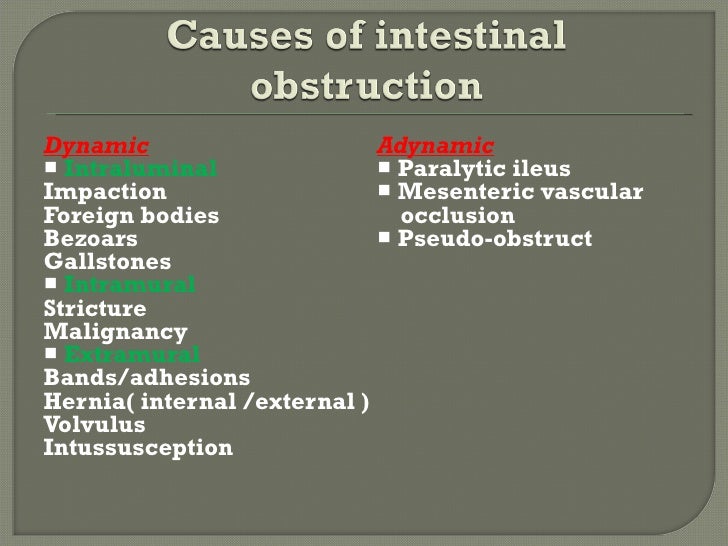

Bowel Obstruction Causes

Acute Intestinal Obstruction Pathophysiology Creative Med Doses

Large Bowel Obstruction Bowel Obstruction Causes Management